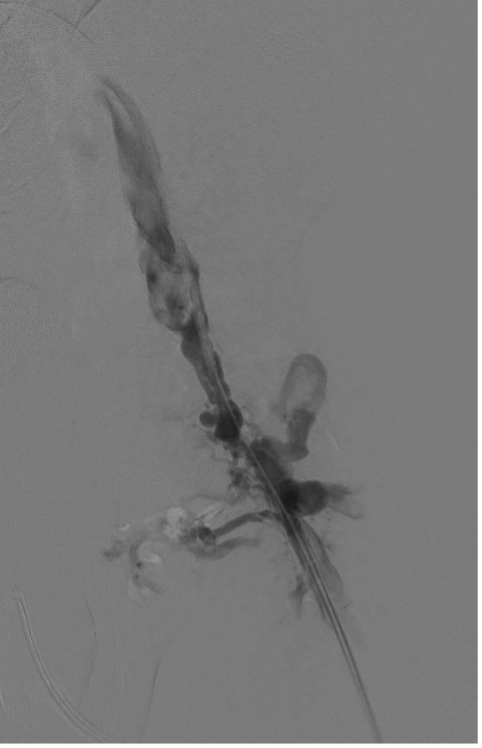

Using both ultrasound and fluoroscopy, we triangulated what we felt to be the appropriate trajectory for recanalization with safest access medial to the artery from a right anterior oblique approach (Figures 5 and 6).

Snare catheters (15-mm Amplatz Goose Neck [Medtronic]) were then placed bidirectionally and advanced to the most distal position in the truncated target channels. These were rotated to the appropriate position for planned recanalization. Percutaneous micropuncture access was then performed with ultrasound and fluoroscopy across both snare catheters, utilizing the modified gun-sight technique10 originally developed by Haskal et al11 (see Appendix).

A 300-cm, .014-inch Fathom wire (Boston Scientific) was placed through the percutaneous needle and snared through each access sheath. With through-and-through access achieved, a direct femoral channel was established. Serial balloon angioplasty was performed with intermittent venography. Intravascular ultrasound (Philips) evaluation was also performed to document the channel. This showed a short segment of “uncovered” tract without visualization of the vein wall. At the same level, venography showed a small amount of extravasation of contrast, as expected. There continued to be filling of the large inguinal collateral veins, even after balloon dilation to 8 mm (Figure 7).